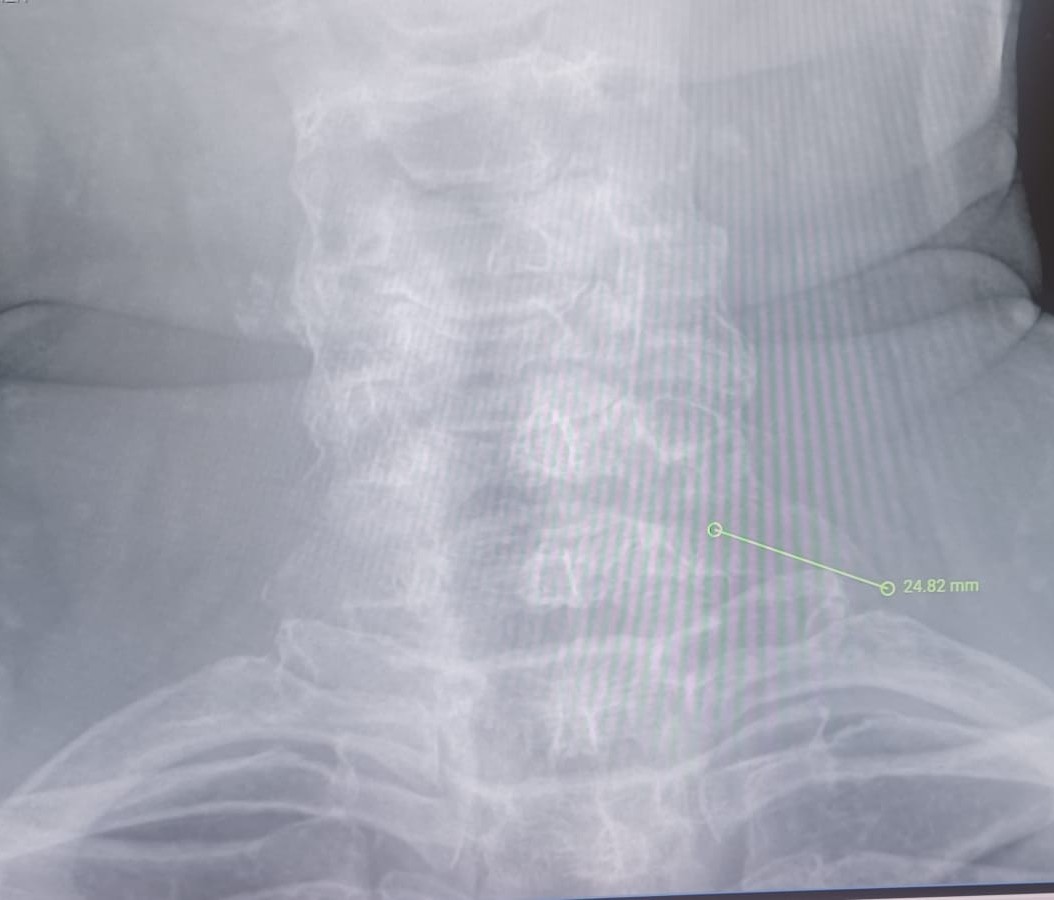

- Apòfisis transverses C7 prominents, callós òssia o anomalies de la primera costella. (Figures 1 i 2)

Figura 1: Procés transversal c7 prominent